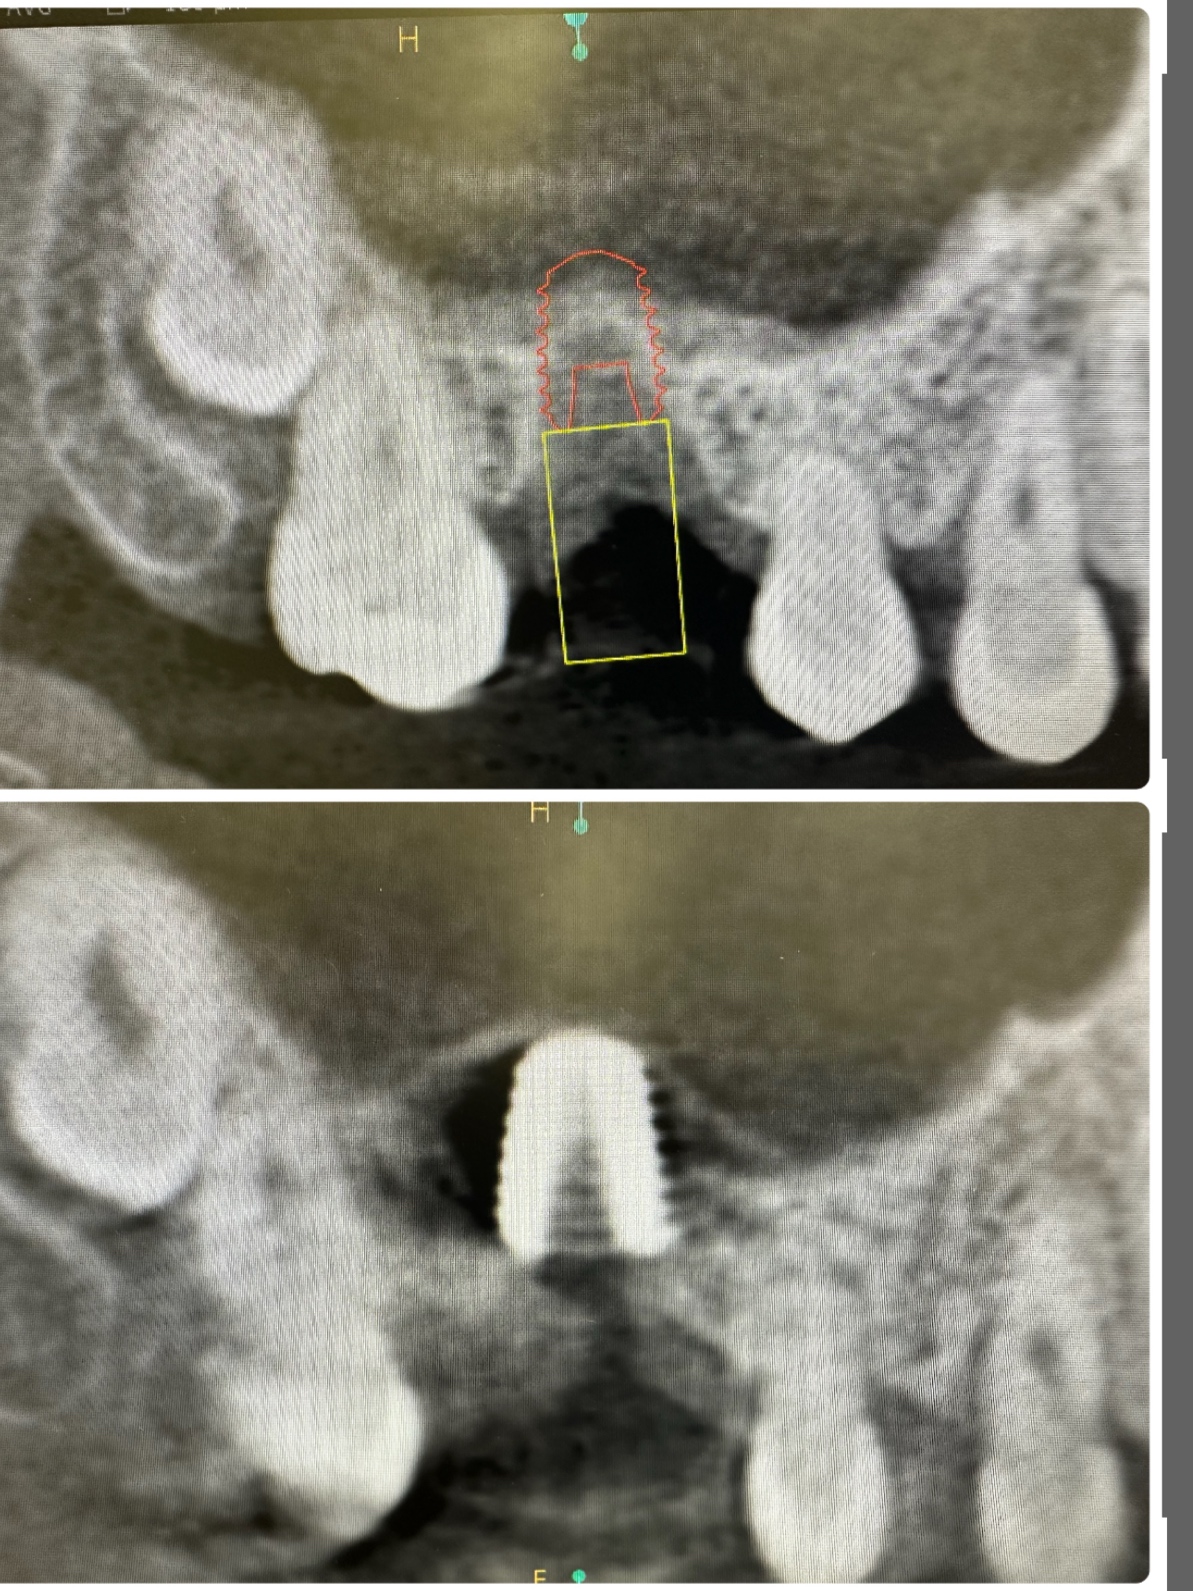

昼間からは、危ない動脈近接のソケットリフト

バッチリ👍避けるコツがある💪

5ミリで骨折、自己採血2本メンブレン挿入

計測値バッチリ75後半👍👌